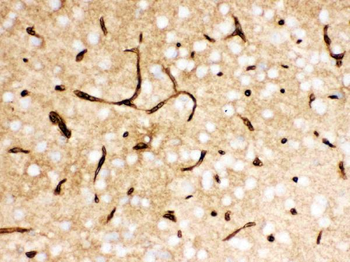

100 μg - PGP9.5 antibody [orb6713]Featured

ELISA, ICC, IF, IHC-P, WB

Human, Mouse, Rat

Rabbit

Polyclonal

Unconjugated